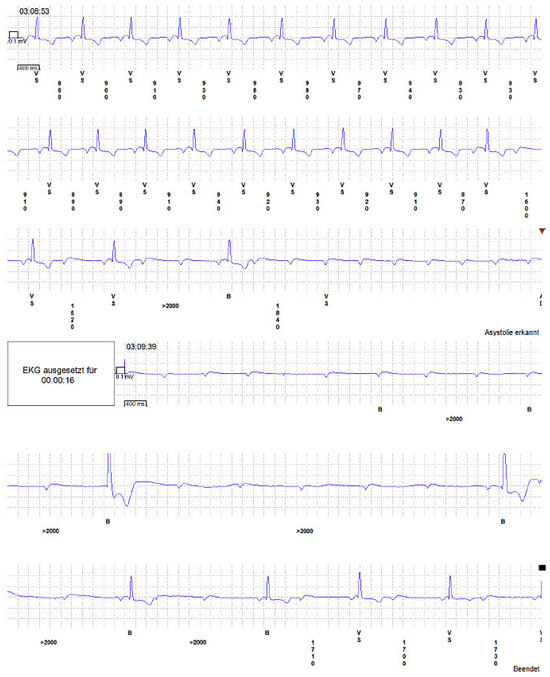

Successful Implantation of an Implantable Loop Recorder in a Patient with Bilateral Silicone Breast Implants Leading to a Diagnosis Explaining Repeated Syncopal Events

by Beeler Remo, Gujer Samuel, Lehmann Dietrich and Kaeslin Thomas

Cited by 1

We report the case of a 54-year-old patient with bilateral silicone breast implants in whom successful implantation of a subcutaneous loop recorder led to the diagnosis that explained her repeated syncopal events. Full article